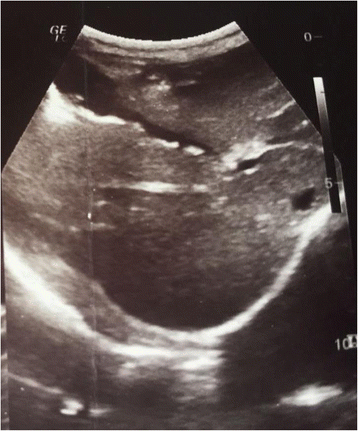

Gallbladder Ascariasis In Kosovo – Focus On Ultrasound And Conservative

jmedicalcasereports.biomedcentral.com fig gallbladder case kosovo ultrasound ascariasis conservative therapy focus series